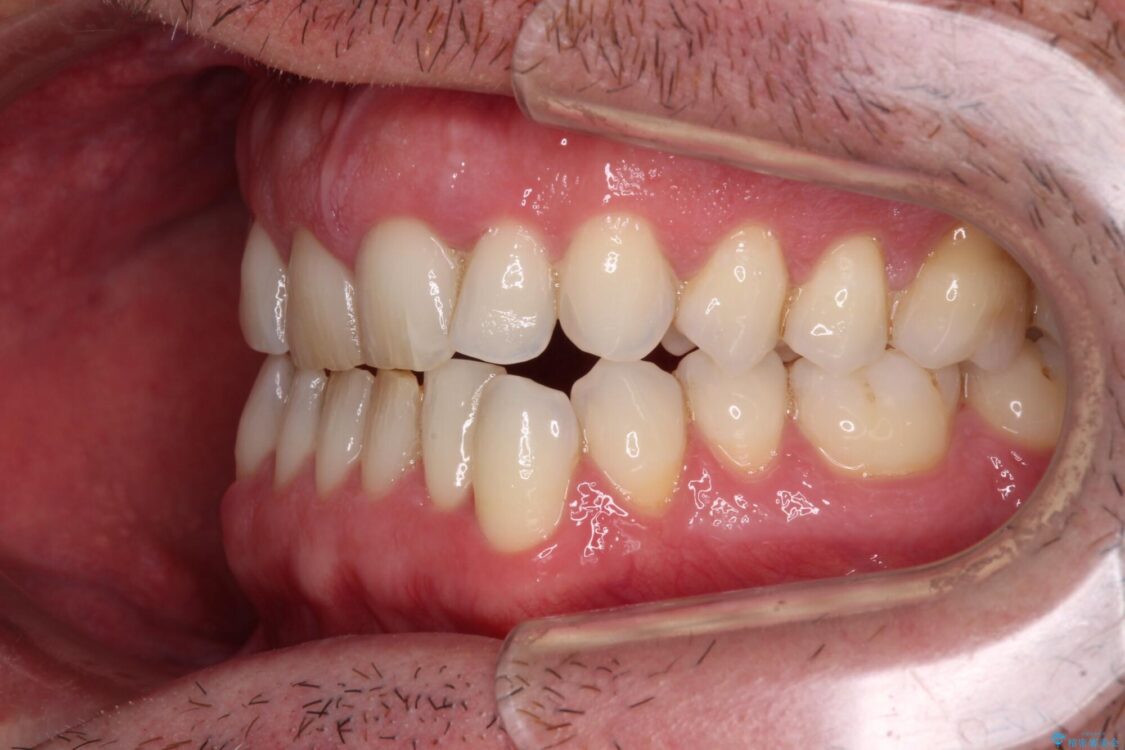

以前矯正治療を経験されたそうですが、舌の突出癖により上下前歯に隙間ができている様子でした。

前歯の非接触改善は、インビザラインの得意とするところですが、マウスピース矯正は絶対に継続できないとのことで、ワイヤー装置にて矯正治療を行うこととしました。

治療前

• 前歯でものを噛みきりたい 目立たない装置でのワイヤー矯正 治療前画像